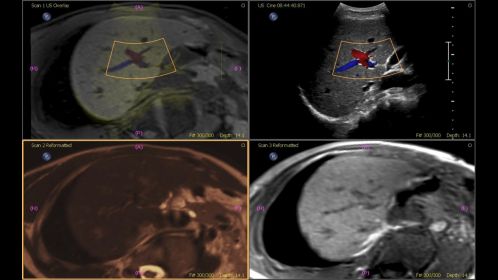

Philips Fusion and Navigation с полностью интегрированными средствами объединения текущего ультразвукового изображения с изображениями КТ, МРТ и ПЭТ позволяют повысить надежность диагностики даже в сложных для диагностирования случаях.

Fusion and Navigation помогает сократить затраты и уменьшить продолжительность процедуры, обеспечивая мультимодальное объединение изображений в различных клинических сценариях. Быстрое и эффективное объединение КТ/МРТ/ПЭТ с УЗИ в реальном времени позволит вам принимать уверенные решения даже в сложных случаях. Fusion and Navigation также может использоваться вместе с контрастной эхографией. Комбинируя методы визуализации непосредственно в ультразвуковой системе, вы получаете доступ к передовым инструментам визуализации, позволяющим быстро принимать решения. Используйте объединение изображений при исследовании брюшной полости, предстательной железы, молочной железы или малых органов, сокращая время и зависимость от других методов визуализации.

В основе устройства лежит наша самая мощная архитектура, которая затрагивает все аспекты получения и обработки ультразвуковых сигналов, позволяя совершенствовать методы ультразвуковых исследований: автоматическая регистрация Auto Registration позволяет Fusion and Navigation обеспечивать успешное объединение объемов по данным КТ или МРТ с данным УЗИ менее чем за одну минуту для эффективного определения характеристик поражений. Регистрация изображений, полученных двумя методами визуализации, обычными способами может быть трудоемкой и технически сложной, часто занимая до 10 минут для достижения успешного объединения. Автоматическое объединение менее чем за одну минуту дает больше времени, чтобы сосредоточиться на предстоящей процедуре, и сокращает время на обеспечение точного объединения.